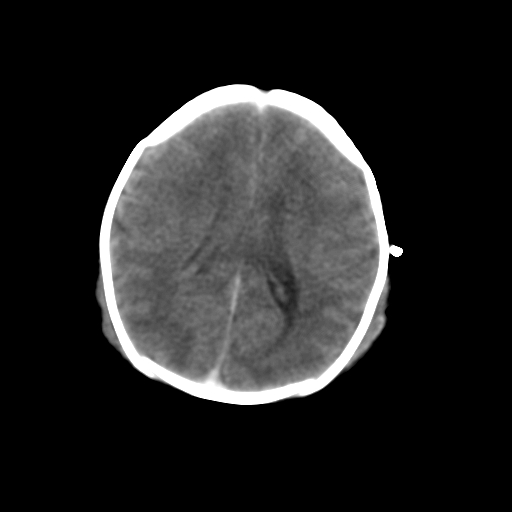

新生儿女2天,有窒息史,经抢救好转!白质最低ct值>23hu,请教各位老师:是否有出血?是否合并缺氧脑病?谢谢!

hie、蛛网膜下腔出血,皮下血舯。

hie、蛛网膜下腔出血,皮下血舯。透明隔间腔形成支持

双侧额叶白质低,白质ct值低于18hu可以考虑水肿改变

后纵裂密度高,前纵裂密度低,比较来说应该考虑有蛛网膜下腔出血

空三角征,蛛网膜下腔出血。